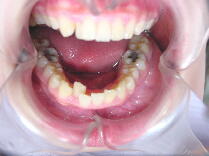

症例2 (20代 女性) 非抜歯例 ![]() ![]() ![]()

初診時平成12年6月